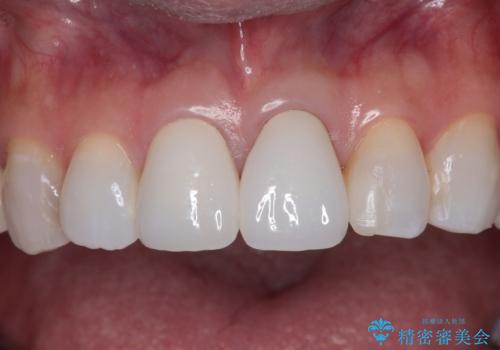

元々の歯の色が非常に白く、セラミッククラウンの色調を合わせるのに苦労しましたが、最終的に大変満足いただけるクラウンを装着することができました。